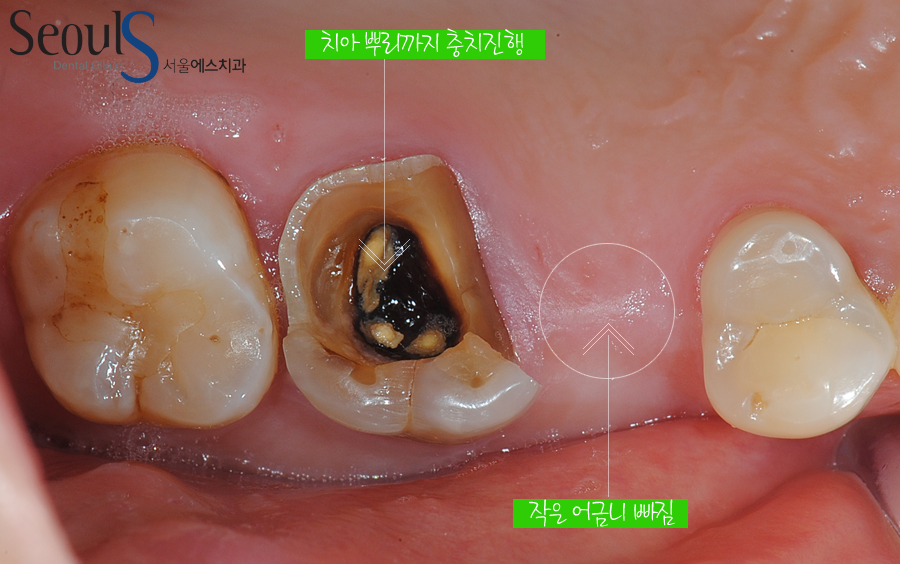

작은 어금니가 빠졌고 큰 어금니는 치아 뿌리까지 검게 충치가 진행되고 있습니다

이런 증례는 치료하면서 좀 안타깝습니다

큰 어금니의 경우 신경치료를 마무리했던 상태인데, 그때 크라운 수복이 이루어지지 않아서

약한 치질이 깨져나가고, 신경치료한 구멍을 통해 세균이 감염돼서

치아 속이 다 썩었습니다

제때 크라운을 했더라면 이렇게 되지는 않았을 텐데, 하는 아쉬움이 있습니다

어쨌건 충치가 치아 속까지 깊게 진행되었고, 치아를 살릴 수 없는 상태였습니다